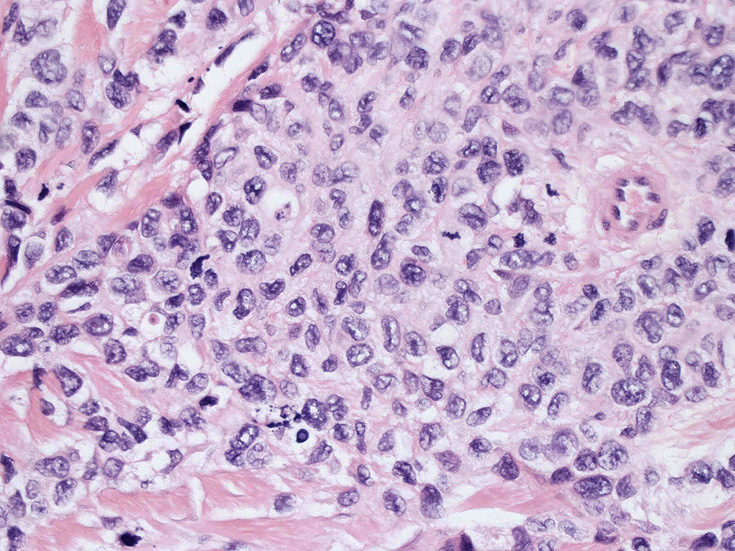

皮膚に異型細胞の浸潤がみられる。異型細胞は表皮内に浸潤するほか、表皮真皮境界部, 真皮, 皮下脂肪組織にもびまん, 結節様の浸潤所見を示す。血管周囲に浸潤、集蔟する所見も多く見られる。 増殖浸潤細胞の核には類円形や腎臓形, またはへこみ, 切れ込み, 溝などを有する多型な核が認められる。クロマチンは粗でvesicularな核が多い。核小体の明らかな核もある。好エオジン性の核内封入体様構造も少数に見られた。mitosisは容易に認められる。hyperchromaticな多型核, bizzarreな細胞が高頻度に認められ異型度は高いと考えられる。細胞質は境界不明瞭, 淡明または泡沫様の 好エオジン性胞体である。

免疫染色 浸潤細胞はCD1a+, S100+, Langerin+, HLA-DR+, CD4+, CD45+, CD68+. MIB-1 index:24.4%

Speaker's Pathological Diagnosis: Langerhans cell sarcoma, skin, rt. knee, biopsy